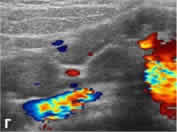

| в - ДДС в цветовом режиме, определяется гиперемия стенки

червеобразного отростка (поперечный срез), лежащего рядом

с подвздошными сосудами. |